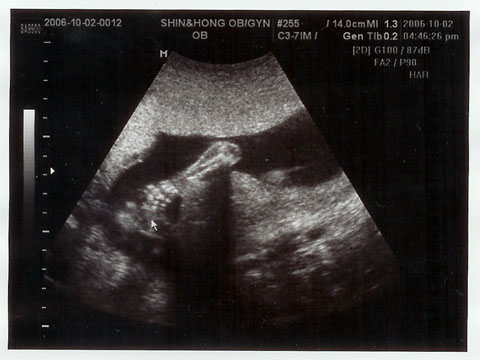

10月2日、お顔を見せて~

先月は一緒じゃなかったので、

「パパにかわいいお顔見せてね~」

って言っておいたのだけど、恥ずかしかったのか、この日はずっとうつむいたまま!

超音波写真もこのとおり。

2枚目の写真は、ひじから先の手。はっきり写ってるでしょ!

起こそうと、先生が何度もお腹を揺さぶったけど、全然起きない我が子…。

ママに似て頑固なのかしら^^;。